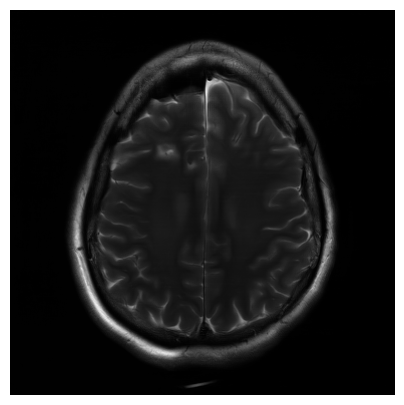

We used the PSNR and SSIM metrics to quantitatively compare the reconstructed magnitude image and the ground truth. They are given for each contrast and for the 2 acceleration factors in the Figs. 2- 3. Similar results are available on the public fastMRI leaderboard333fastmri.org/leaderboards, although generally slightly better. It is a bit difficult to consider these results when compared to only the zero-filled metrics, but these quantitative metrics do not accurately capture the performance of the GRAPPA algorithm [2]. However, at the time of submission, this approach ranks 2nd in the fastMRI leaderboards for the PSNR metric, and finished 2nd in the 4 and 8 tracks of the fastMRI 2020 brain reconstruction challenge [16].

Qualitative.

The visual inspection of the images reconstructed (available in Fig. 2) at acceleration factor 4 shows little to no visible difference with the ground truth original image. However, when increasing the acceleration factor to 8, we can see that smoothing starts to appear which leads to a loss of structure as can be seen in Fig. 3.

| T1 PSNR: 41.56 SSIM: 0.9506 | T2 PSNR: 40.68 SSIM: 0.9554 | FLAIR PSNR: 39.60 SSIM: 0.9321 | T1POST PSNR: 42.53 SSIM: 0.9683 |